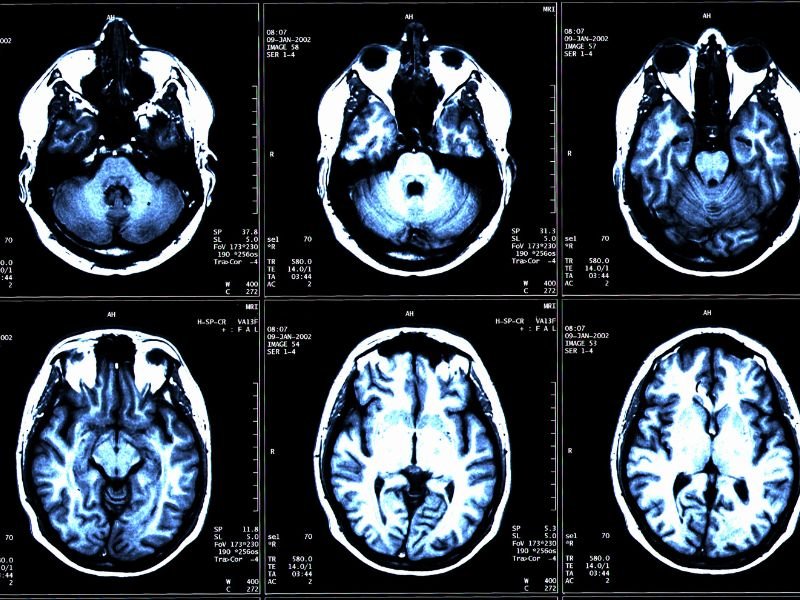

Tratamento Avançado para Enxaqueca em Tubarão A enxaqueca é uma condição neurológica que afeta milhões de pessoas em todo o mundo. Em Tubarão, o tratamento avançado para enxaqueca tem se tornado uma prioridade para muitos